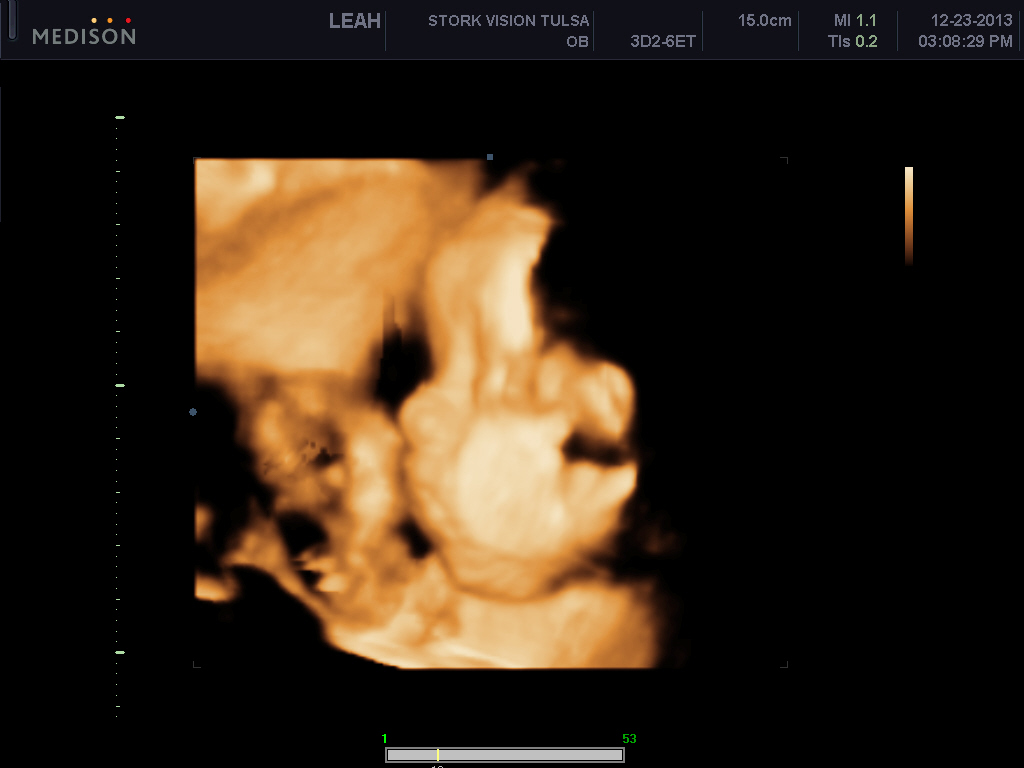

I want to AW my sons 3d ultrasound! :) PIP heavy

He's freaking adorable! These are my favs out of about 70 pictures..

These ones below show him stretching and its just so cute to me!!